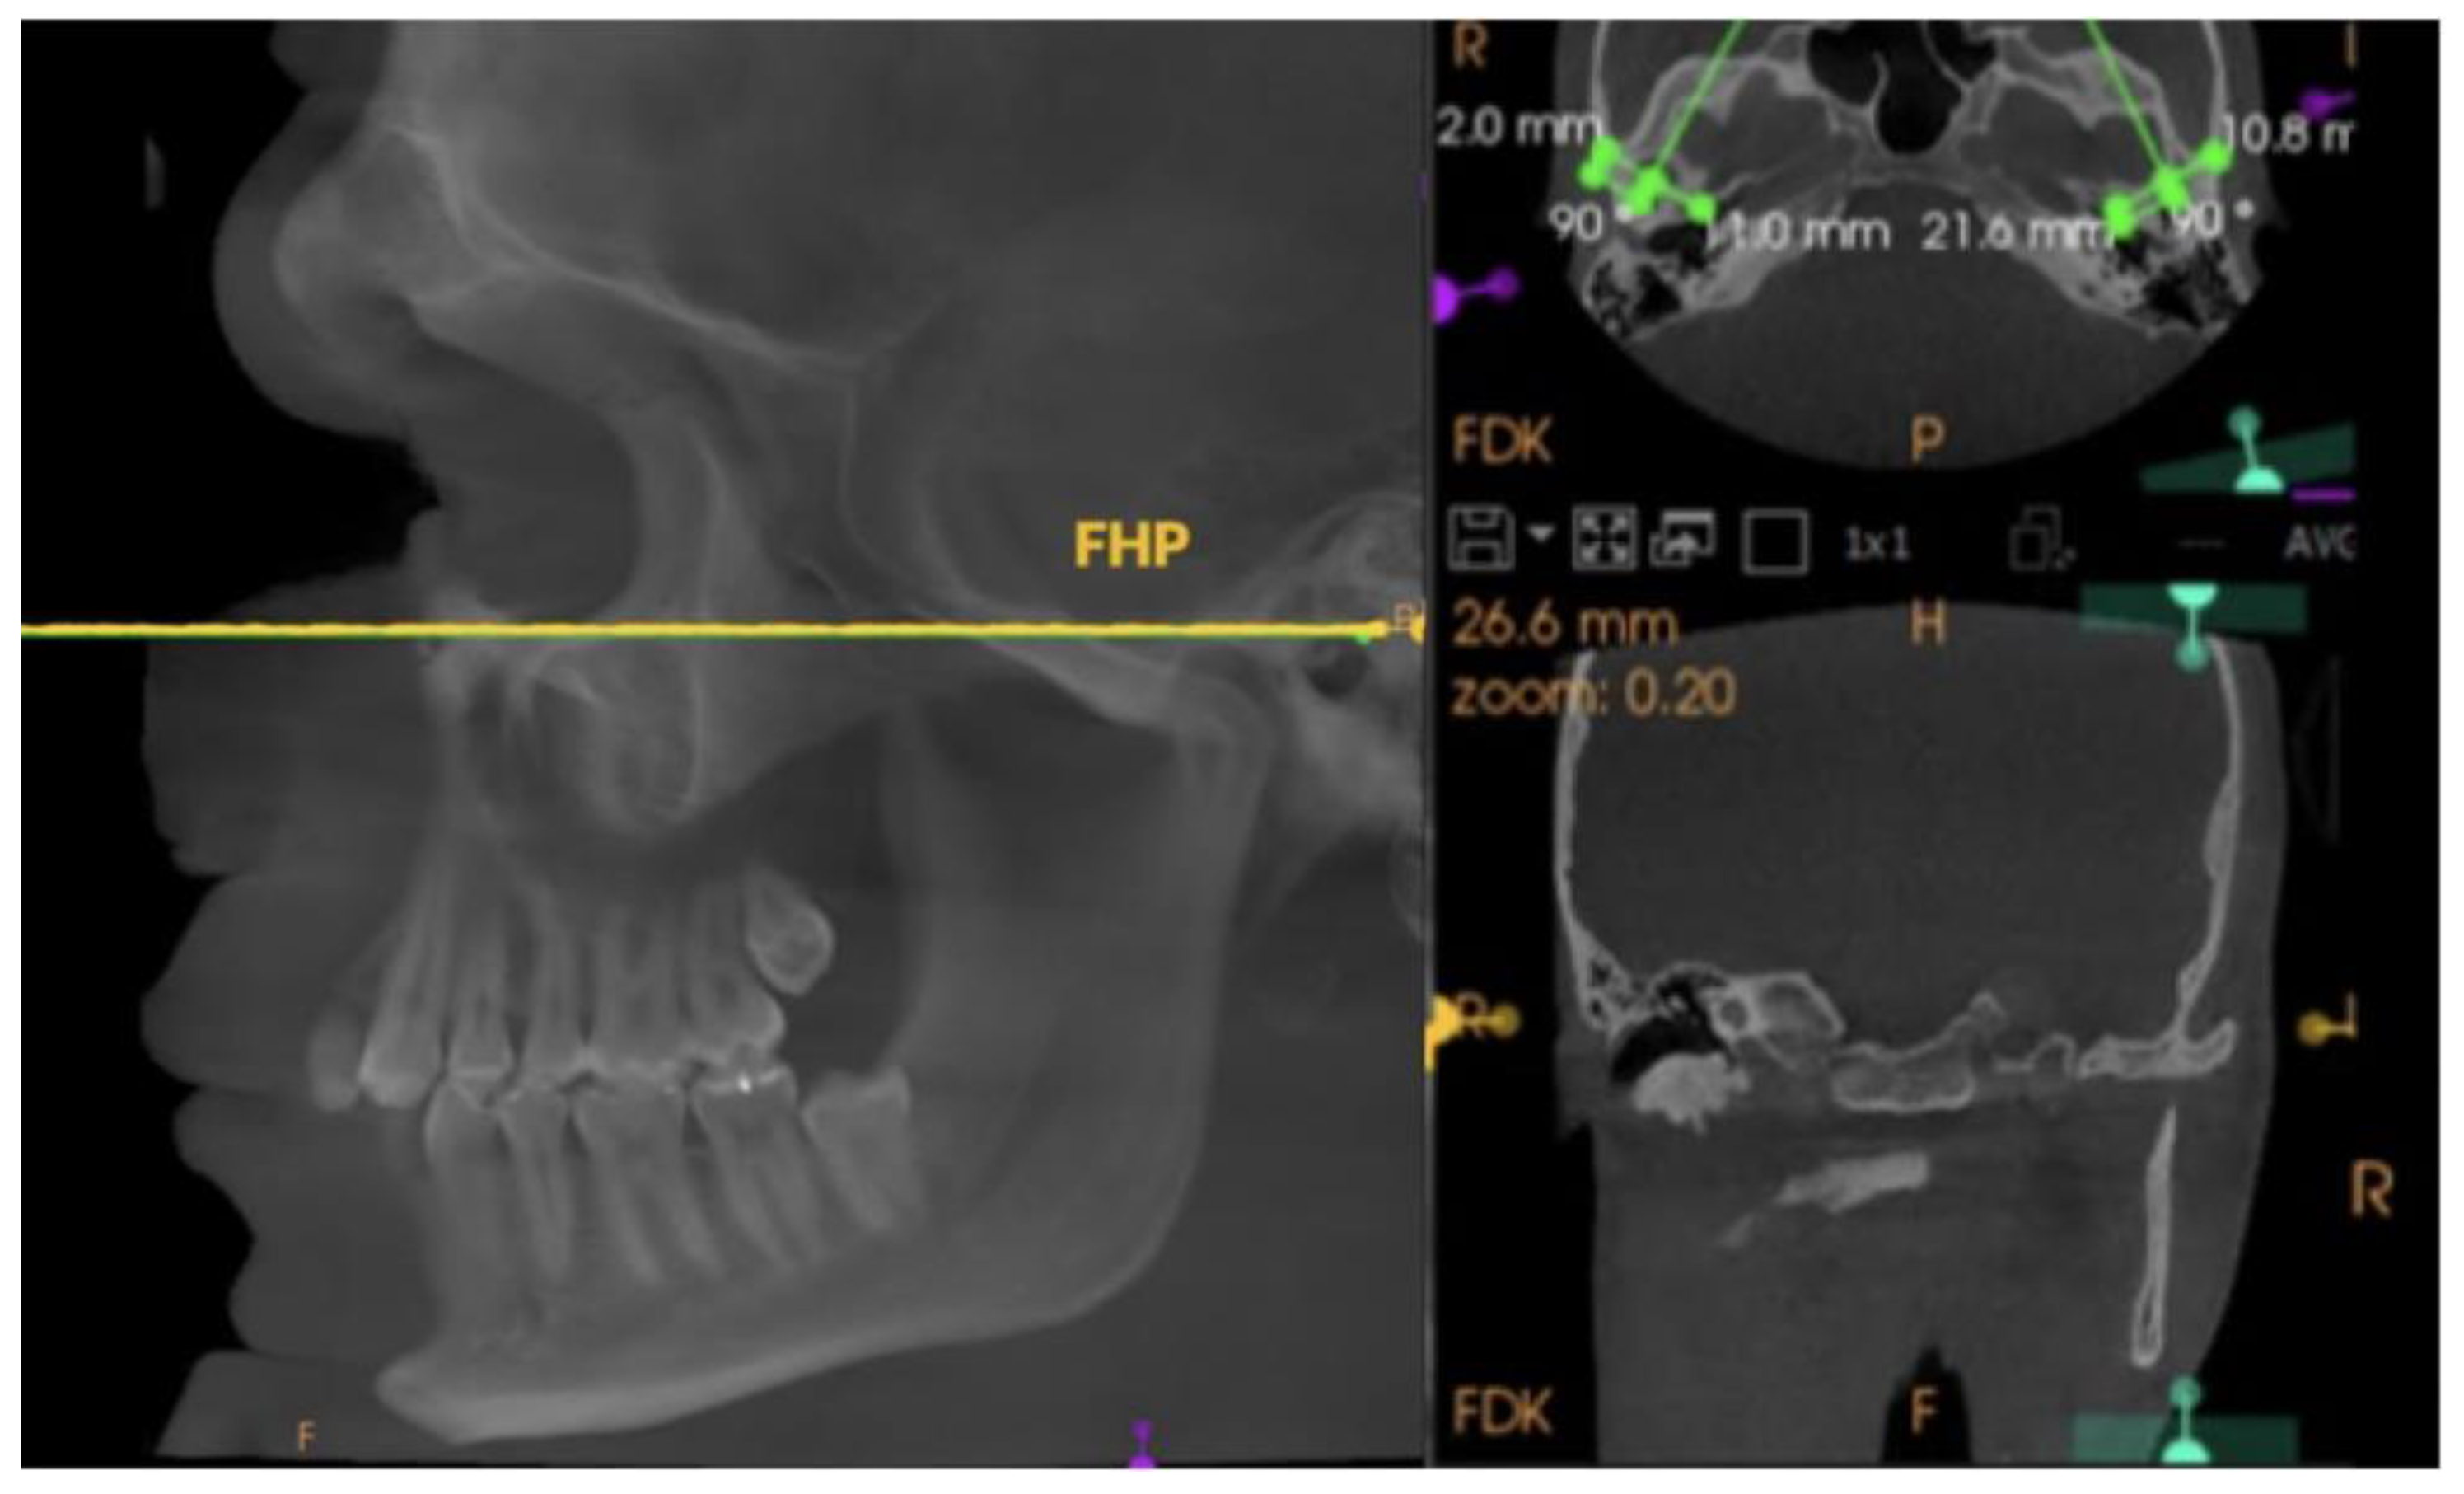

Comparison of Condylar Guidance in Opening and Protrusion Using Electronic Axiography and CBCT: An Observational Cross-Sectional Study

2. Materials and Methods